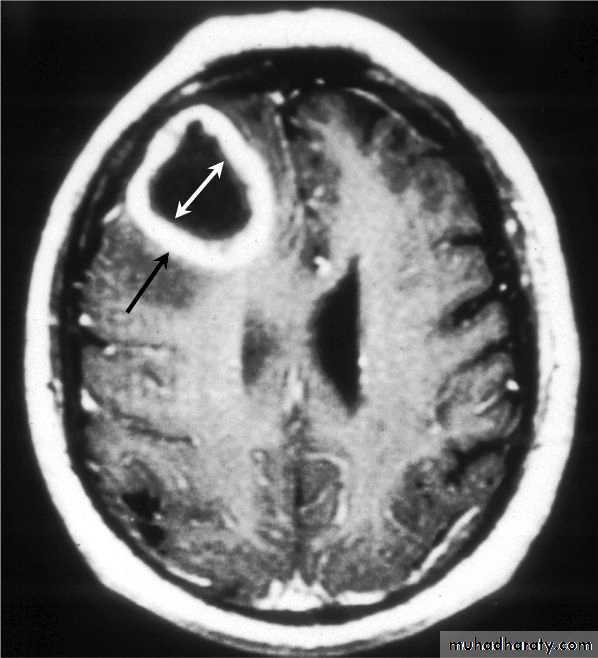

Brain Abscess MRI

• They will show a single (or multiple) space occupying lesion that is well delineated with an enhancing wall, with variable surrounding oedema.

• B. Radiological Investigations:• CT or MRI is the investigation of choice.

• CT Brain is performed with and without contrast.

• MRI is done with gadolinium enhancement.